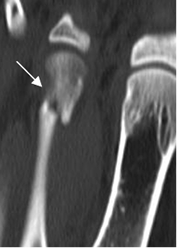

Fig 35. Fractura de stress.

TAC reconstrucción axial. Fractura en el metatarsiano, con incipiente formación de callo óseo.